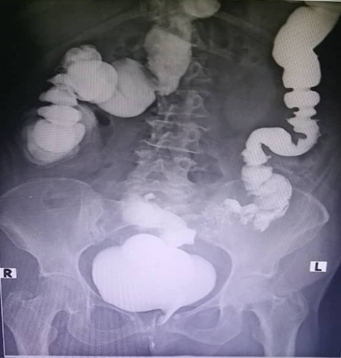

61-year-old white female patient with previous health history (hysterectomy for uterine fibroid 02-03-2000). Who comes to our service for presenting pain in the lower abdomen, pneumaturia and fecaluria. On physical examination, a 5x7 cm tumor in the hypogastrium of hard consistency, with irregular edges, non-mobile and painful is palpable. Abdominal ultrasound is performed which reports a heterogeneous image of 7x6.5 cm supravesical in intimate relationship with the sigmoid colon, a contrasted abdominal computed tomography is requested (Figure 1), which reports intravesical hydroaereal level. A cystoscopy was performed, which confirmed our diagnostic suspicion of a colovesical fistula, and a biopsy punch was taken, which reported well-differentiated adenocarcinoma. A colon is performed by enema with water-soluble contrast (Figure 2), observing the colovesical communication, gorge image (sigmoid colon neoplasia), and addition images (sigmoid colon diverticulosis). With all the above elements, the patient is announced under the diagnosis of colovesical fistula, performing sigmoidectomy and partial cystectomy with immediate colorectal anastomosis and cystorrhaphy complemented with a catheter cystotomy (bladder carving). The patient evolves favorably and is discharged on the tenth day. The biopsy reports a well-differentiated mucoproducer adenocarcinoma.

Figure 2 It shows the abnormal communication between the sigmoid colon and the bladder. In addition, an image of the gorge and addition images are observed.

The most common cause of colovesical fistula is diverticular disease of the sigmoid colon (66-75% of cases).3–5 The underlying mechanism is the direct extension of a ruptured diverticulum or the erosion of a peridiverticular abscess into the bladder, and the mechanism by which colon cancer can take the bladder abscess from the tumor or infiltrate the bladder dome. Most patients (> 90%) with colovesical fistula usually present with recurrent urinary infections and dysuria. Pneumaturia is present in 71% -90% of cases and fecaluria in 51% -76%, both signs considered pathognomonic signs of FCV.5,6 For diagnosis, cystoscopy visualizes the lesion in almost 90% of patients. In some cases, CT with contrast in the rectum and sigmoids helps to localize the abnormal communication. In our case, we use what we believe to be the tripod for the topographic and etiological diagnosis of this entity, such as cystoscopy, contrast abdominal tomography and the colon by enema with water-soluble contrast. The first can observe the abnormal communication, can see elements of chronic cystitis, presence of intravesical air and taking a biopsy of the lesion, in the second shows an intravesical air-fluid level, which is pathognomonic, defines thickening of the walls and defines etiology (diverticular disease or tumor of the sigmoid colon), the third study shows the abnormal communication clearly, precise etiology images of addition in the diverticular origin and images of stenosis or defile in the malignant cause. Bannura et al.1 mention computerized axial tomography as the gold standard for the diagnosis of this entity, followed by barium enema and cystoscopy.